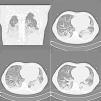

The consolidation areas had a peribronchovascular and subpleural predominance and were found mainly in the middle and upper zones of the lung (Fig. 2). Reticular opacities were found in six cases. The most outstanding CXR and chest CT features of the disease were basal and axial interstitial-alveolar consolidation and ground-glass opacities (Fig. 3): the extent of disease was greater in Group 1 (patients requiring mechanical ventilation) with a greater number of lobes involved and a greater CXR score (p<0.001). Airway thickening and dilatation, small airway involvement with centrilobular nodules and tree-in-bud opacities was not found.

A 39-year-old man with Influenza A (H1N1) virus pneumonia and severe respiratory failure (PaO2/FIO2 at admission 170) respiratory underwent non-invasive mechanical ventilation: chest computed tomography shows alveolar consolidation, peripheral ground-glass opacities in both middle and lower lung zones and small bilateral pleural effusions.